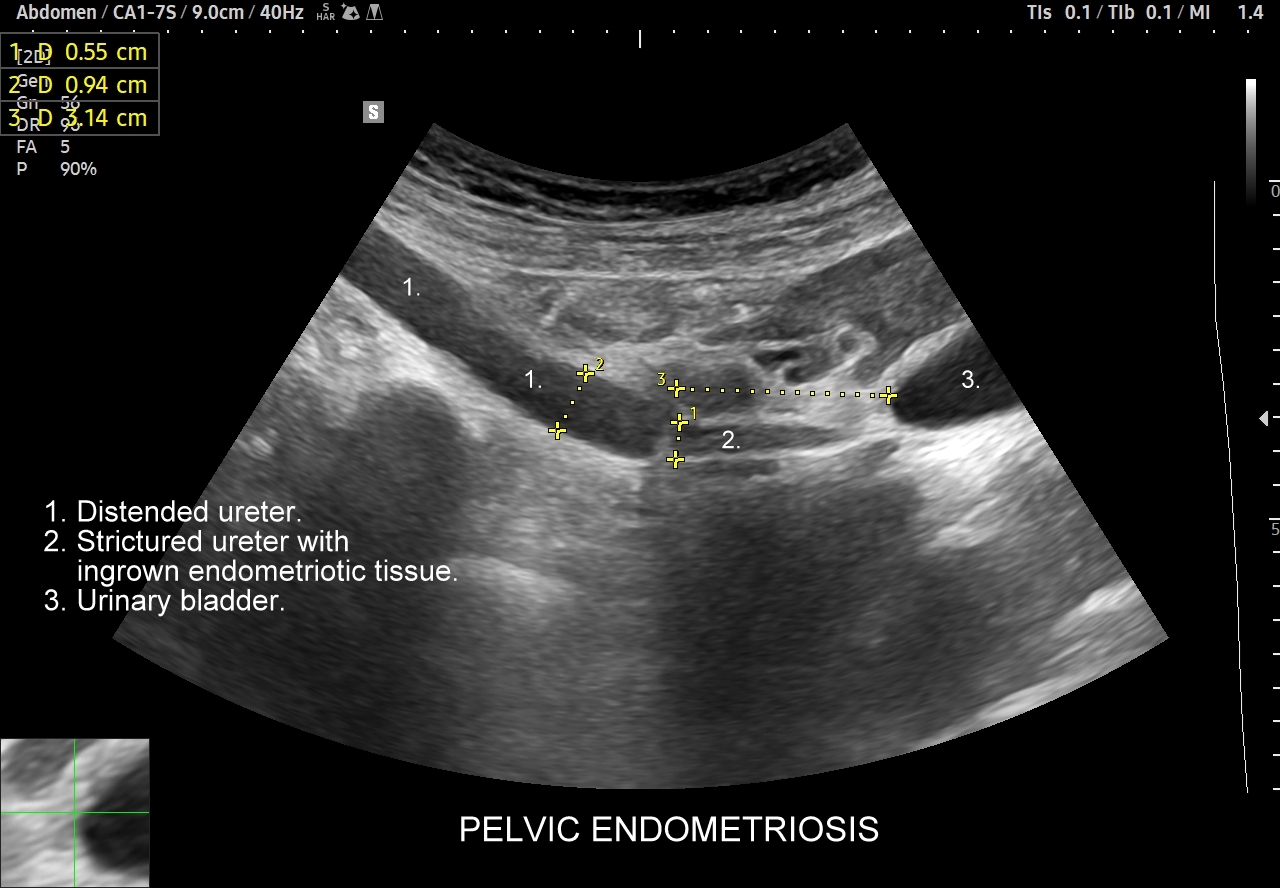

Warsztaty USG / MPUS obszaru brzucha Cedum ® przeznaczone są dla lekarzy chcących pogłębić oraz usystematyzować swoją wiedzę, poznać triki i praktyczne wskazówki, zaznajomić się z zaawansowaną obsługą aparatury USG, a także pracować z pacjentem pod nadzorem tutora. Podczas praktycznego szkolenia USG dla lekarzy uczestnicy praktycznie i samodzielnie badać będą narządy wewnętrzne i duże naczynia jamy brzusznej, oceniać przepływy wątrobowe oraz nerkowe, będą używać trybów elastograficznych, a w multiparametrycznym badaniu MPUS będą funkcjonalnie oceniać wątrobę i nerki. Szkolenie USG obejmuje również ocenę powłok brzucha oraz pachwin.

Multiparametryczne badanie USG (MPUS) jest rozwinięciem klasycznego USG jamy brzusznej zwykle w formie jednoczasowego zastosowania różnorodnych technologicznie trybów obrazowania USG, zarówno tzw. „nowych”, jak i „starych”. Wśród nowych najważniejszym jest obrazowanie mikrounaczynienia (MVI / MVF), a w dalszej kolejności tryby elastograficzne oraz metody ilościowej oceny stłuszczenia wątroby. Wymienione „nowe” modalności w połączeniu ze „starymi”, przede wszystkim z Dopplerem spektralnym i color-Dopplerem, stanowią rdzeń nowoczesnej ultrasonografii MPUS, gdyż umożliwiają pozyskanie znacznie większej ilości informacji z badania USG w porównywalnym przedziale czasowym, a przez to uzyskanie jego większej wartości diagnostycznej. Przykładowo badanie MPUS umożliwia różnicowanie pseudoguzów od guzów prawdziwych, ocenę żywotności tkanek, biologii nowotworów, funkcjonalną ocenę nerek i wątroby, poprawia obrazowanie dużych naczyń krwionośnych oraz charakterystykę podejrzanych torbieli.